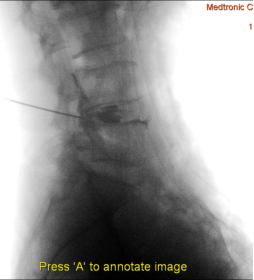

(1)患者采用俯卧位,提前设置好O型臂多维外科成像系统所需扫描定位平面(图1,图2),在正位透视下标定一条腰椎棘突中线,再沿髂棘最高点做一水平线,腰5骶1椎间盘正侧位的透视交叉点,即为穿刺点,一般在中心线旁开10-12cm左右处选一穿刺点。此线为穿刺的方向和角度(图3)。

图1 定位椎间隙 正位

图2 定位椎间隙 侧位